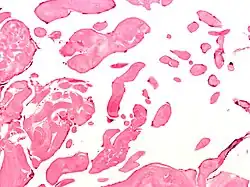

| Low magnification micrograph of an excised aortic valve papillary fibroelastoma showing the characteristic avascular branching papillae, H&E stain | |

Papillary fibroelastoma are typically found and accurately diagnosed by imaging. The diagnosis is confirmed by pathology. Histologically, papillary fibroelastomas have branching avascular papillae, composed of collagen, that are covered by endothelium.